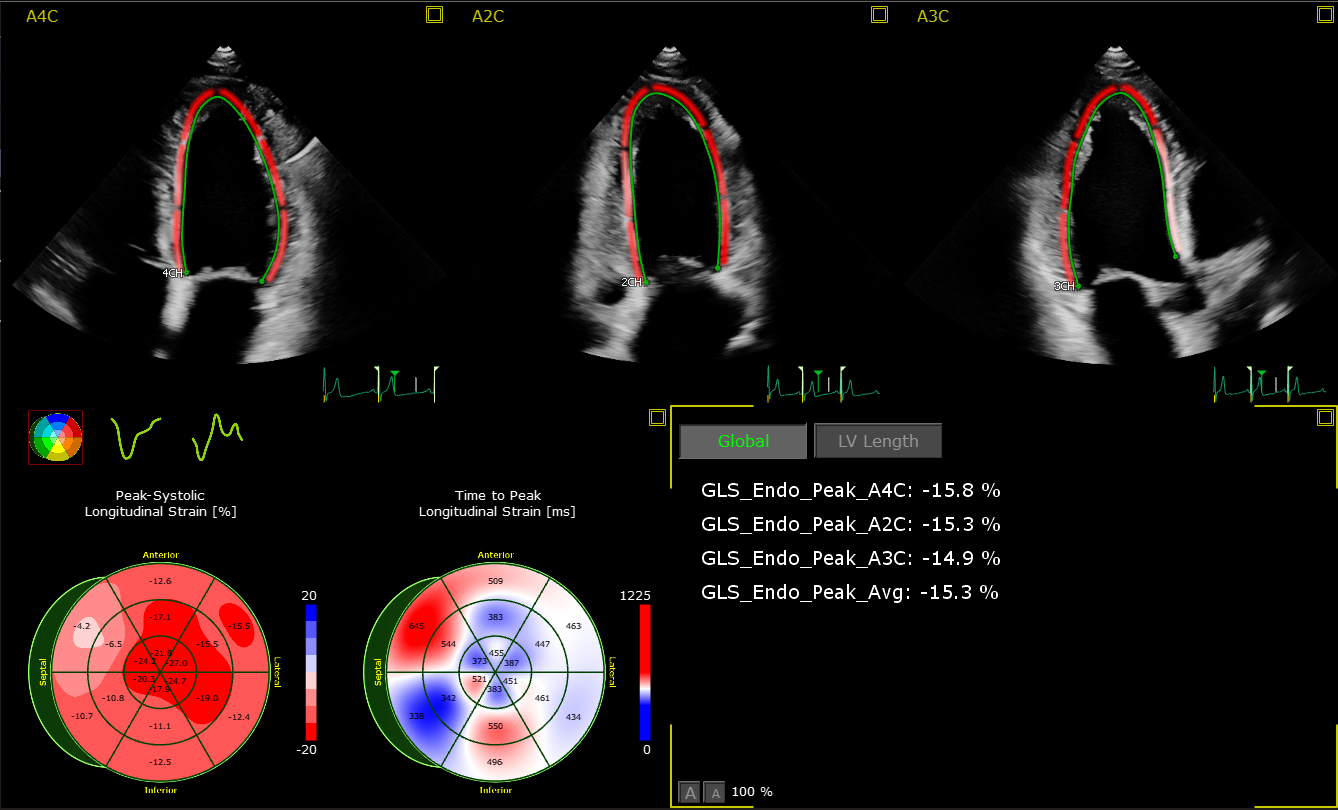

The AutoStrain LV application uses advanced Automatic View Recognition technology to identify the different views of the heart, providing exceptional visualization and analysis of left ventricular function – extremely important diagnostic information for patients at risk of developing cardiovascular disease. Also available are AutoStrain LA and AutoStrain RV, applications which automate the measurement of left atrial and right ventricular longitudinal strain respectively. By creating reliable and reproducible strain measurements for the left ventricle, left atrium and right ventricle, the AutoStrain LV, LA and RV applications support clinicians treating patients with atrial fibrillation, arrhythmia and other complex heart conditions.

The 3D Auto RV application segments, identifies the borders of and aligns the views of the right ventricle, enabling clinicians to carry out the quantification and check the measurements in as little as 15 seconds [3]. These new applications expand on the advanced automation applications already available on the EPIQ CVx platform, including Dynamic HeartModel, which provides a clear vision of the heart’s chambers and how well they are pumping blood – specifically on the left side, where heart failure often begins. A recent study of Dynamic HeartModel published in the European Heart Journal – Cardiovascular Imaging concluded that ‘the automated algorithm can quickly measure dynamic left ventricle and left atrial volumes and accurately analyze ejection/filling parameters’ [4].